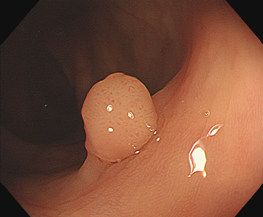

所以检查中发现比较小的息肉(小于0.5cm的)可以顺便切除,并不会感觉到疼痛。

1、比较大的息肉,在无麻醉切除过程中也会产生牵拉疼,患者会不自觉地挪动身体,这样会影响肠镜医生对肠镜以及手术刀的把控;

3、有的息肉基底比较宽,盲目直接切除会有出血的风险;